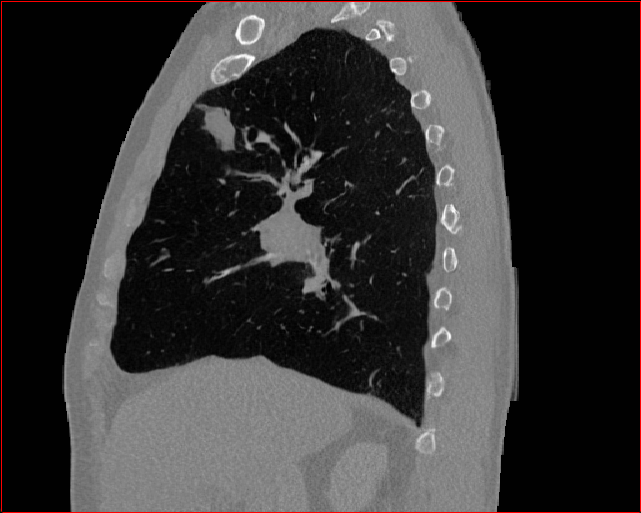

Figure 2: Qualitative comparison across axial (top row), sagittal (middle row), and coronal (bottom row) views. Columns correspond to different methods. MAISI-DDPM and MAISI-v2 in this figure are unconditional synthesis which do not use ControlNet or segmentation maps.

Qualitative Evaluation:

Figure 2 presents representative slices from the axial, sagittal, and coronal planes. GenerateCT (hamamci2024generatect) is a 2D model, so it lacks inter-slice consistency, leading to poor image quality in the sagittal and coronal views. MedSyn (xu2024medsyn) produces noticeably blurry results with mosaic-like artifacts, such as region inside the red box. HA-GAN (sun2022hierarchical) generates visually sharp images but with mosaic-like artifacts, such as region inside the red box. Also, its voxel spacing is not available, which limits its applicability in real-world medical imaging tasks. Moreover, all three methods are restricted to synthesizing small anatomical regions. In contrast, both MAISI and MAISI-v2 are capable of generating high-quality 3D volumes that span larger body regions while preserving fine anatomical details and realistic structure.